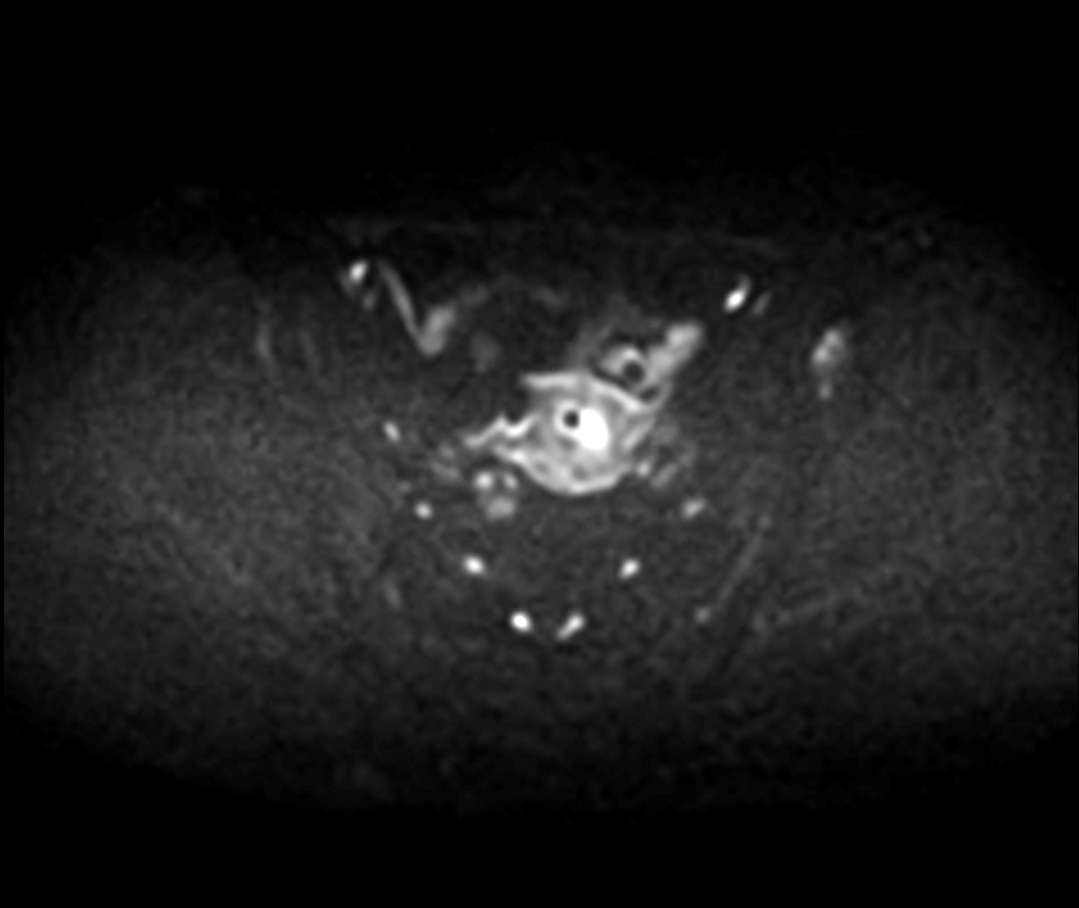

Patient with cervical cancer referred for MR-guided brachytherapy. MR imaging on Ingenia 1.5T with tandem-ring applicator in place for brachytherapy planning.

Axial DWIBS